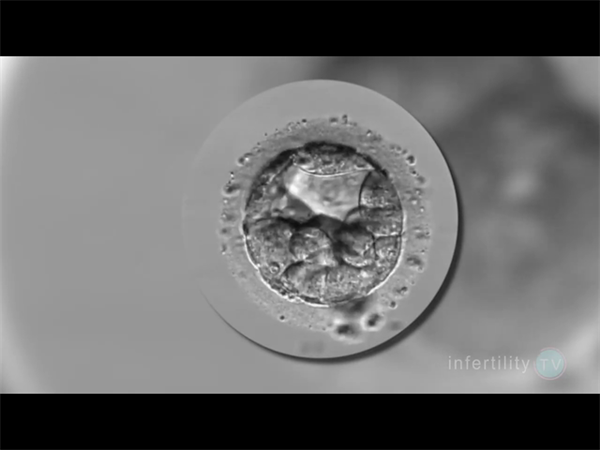

囊胚筛查正常大多不会胎停,出现这种情况大多可能是生殖免疫异常而导致的。一个胚胎,如果能够经过染色体筛查是正常的,那我们说这个胚胎应该是能够在正?;肪诚路⒂商ザ?,并且最终出生的,但是所移植的胚胎并没有最终发育成胎儿。因此我们基本可以断定,是生殖环境不好所导致的。